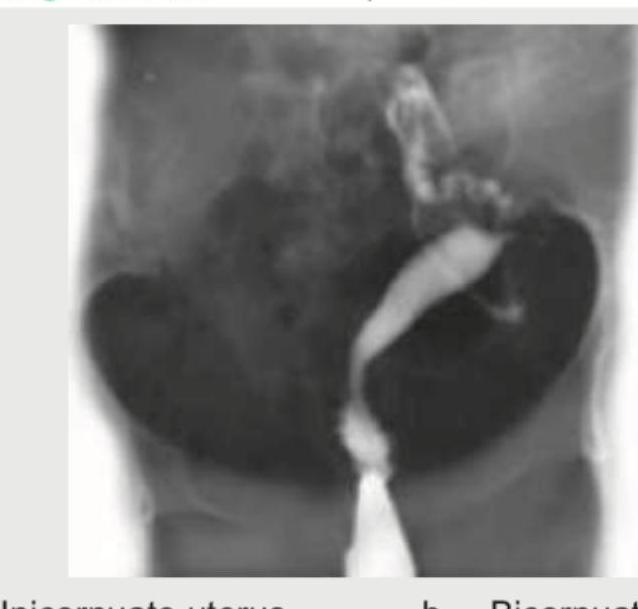

A 32-year-old lady presents with history of first trimester miscarriage and underwent HSG. The diagnosis is: (Recent NEET Pattern 2018-19)

Explanation: ***Unicornuate uterus*** - A **unicornuate uterus** develops from one **Müllerian duct**, resulting in a single functional uterine horn with a characteristic **banana-shaped** or crescent-shaped cavity. - On **HSG**, it appears as a single, elongated cavity that **deviates to one side** and is typically smaller than normal, associated with increased risk of **first trimester miscarriage**. *Bicornuate uterus* - Would show **two distinct uterine horns** separated by a deep fundal cleft, with the uterus appearing **heart-shaped** externally. - HSG would demonstrate **bifurcation** of the uterine cavity into two separate horns at the fundal level with an **intercornual angle >105 degrees**. *Uterus didelphys* - Complete duplication with **two separate uterine bodies**, cervices, and often vaginas resulting from total failure of **Müllerian duct fusion**. - HSG would show **two completely separate uterine cavities** with no communication, not consistent with the single cavity shown. *Arcuate uterus* - Mildest form of **Müllerian anomaly** with only a slight **fundal indentation** and essentially normal uterine cavity size. - HSG shows a **broad, smooth, mild concave contour** of the fundus, not consistent with the elongated, deviated cavity shown.